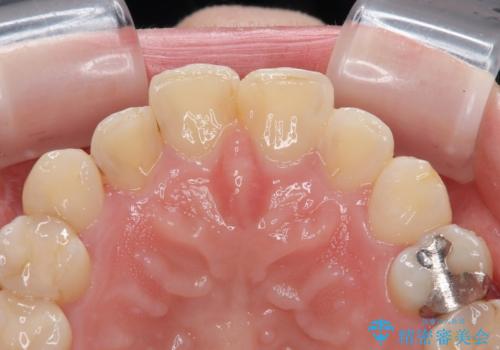

- 前歯の色味が気になるとのことで来院された患者様です。今までに保険のプラスチック(コンポジットレジン)で虫歯の治療をしており経年的な劣化により着色が目立つようになっていました。また歯と歯の隣り合っているところに段差もあり虫歯になっているところもあったため前歯6本のオールセラミッククラウンによる治療を行うこととなりました。

拡大鏡視野下で保険のプラスチック(コンポジットレジン)、虫歯を除去し、オールセラミッククラウンに適した形にしました。